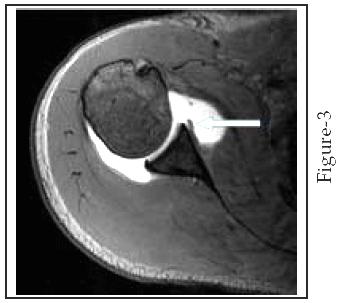

At arthroscopy, 21 anteroinferior labroligamentous lesions were diagnosed, including 15 Bankart lesions Fig (1,2),3 ALPSA lesions(Fig-3), 2 Perthes lesions (fig-4), and 1 GLAD lesion (Fig-5). Seven labral lesions were nonclassifiable at arthroscopy, all of which occurred after a history of chronic instability. When compared with arthroscopic findings, Shoulder MR Arthrography had two false-negative results (sensitivity, 92.8%) and no false-positive results. The sensitivity of Shoulder MR Arthrography in detecting anteroinferior labroligamentous lesions was 92.8% (26/28), and specificity was (100%). The overall accuracy of Shoulder MR Arthrography in detecting labroligamentous lesions in our study was 90.5% (19/21).

Fig-3: ALPSA Lesion. T1-weighted MR arthrogram of the left shoulder in a 24-year-old man with chronic shoulder instability. It demonstrates medial displacement of the labral ligamentous attachment (arrow) consistent with ALPSA lesion.